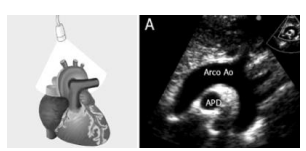

A imagem acima mostra qual tipo de corte?